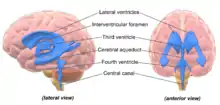

The system comprises four ventricles:[5]

- lateral ventricles right and left (one for each hemisphere)

- third ventricle

- fourth ventricle

The four cavities of the human brain are called ventricles.[6] The two largest are the lateral ventricles in the cerebrum, the third ventricle is in the diencephalon of the forebrain between the right and left thalamus, and the fourth ventricle is located at the back of the pons and upper half of the medulla oblongata of the hindbrain. The ventricles are concerned with the production and circulation of cerebrospinal fluid.[7]

- The prosencephalon divides into the telencephalon, which forms the cortex of the developed brain, and the diencephalon. The ventricles contained within the telencephalon become the lateral ventricles, and the ventricles within the diencephalon become the third ventricle.

- The rhombencephalon divides into a metencephalon and myelencephalon. The ventricles contained within the rhombencephalon become the fourth ventricle, and the ventricles contained within the mesencephalon become the aqueduct of Sylvius.